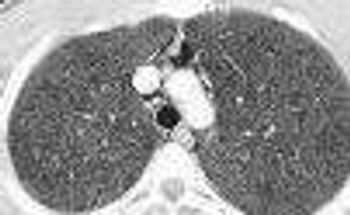

Spontaneous pneumomediastinum with subcutaneous emphysema is rare. Alveolar rupture allows air to enter the pulmonary interstitium and penetrate the mediastinum.